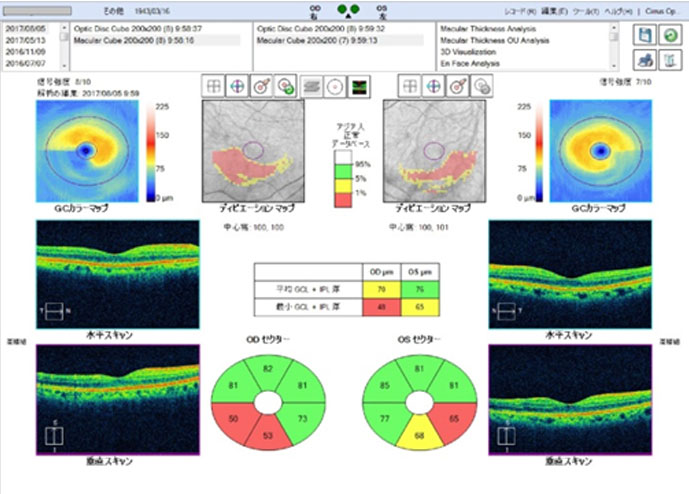

最近この判断を助ける上での画期的な検査機器が登場しました。眼底三次元画像解析装置(OCT)とよばれるもので、近赤外線レーザーを用いて眼底の視神経乳頭の変化や網膜視神経線維層の厚みの変化を正確に判定出来るようになったのです。当院はOCTをいち早く導入し、緑内障を示唆する異常がありながらも、通常の視野検査でまだ視野欠損を認めない状態である前視野緑内障(preperimetric glaucoma:PPG)を検出することができます。緑内障は早期発見早期治療が基本ですので、超早期緑内障の治療を早期に発見をして経過観察を行っていくことは、緑内障の患者様にとって大切であると思っております。

GCA

GCA

緑内障の早期発見の為に、特に前視野緑内障の検出に非常に有用なOCT検査を精密視野検査やその他の検査と併せて行っております。ドックや健診で乳頭陥凹と指摘された方は勿論、近視の強い方や、家族に緑内障患者さんがおられる方は特に早めの検査を受けるようにお勧めしております。病状によりハンフリー視野検査 ゴールドマン視野検査 視神経乳頭解析 GCAを3〜6ヶ月に行い、進行をグラフ化して経過観察を行います。